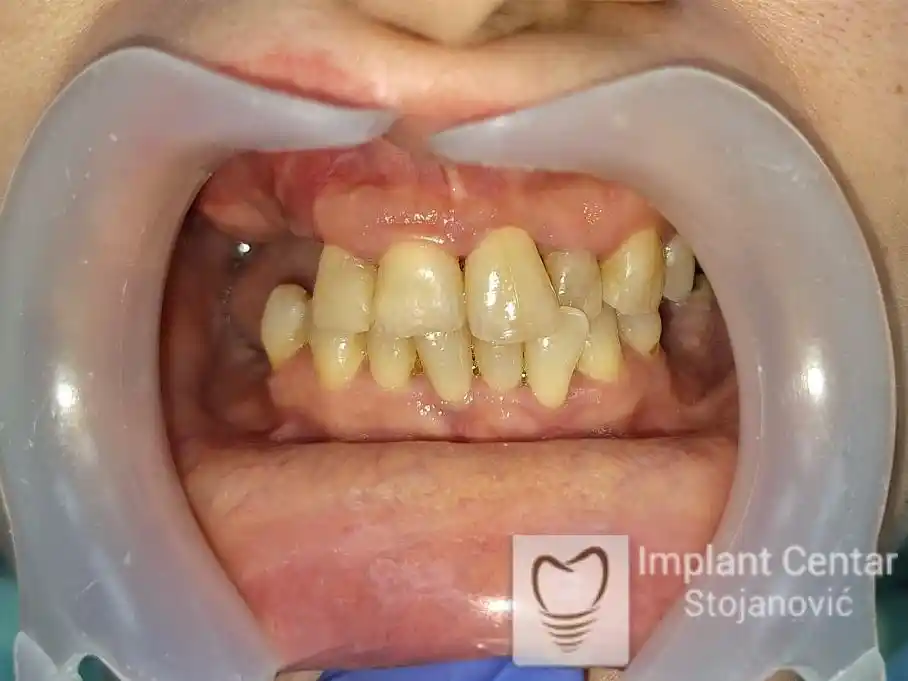

Na slikama 1, 2, 3 , 4  i  5 prikazan je izgled pacijenta pre početka terapije. Nakon detaljne kliničke i radiološke analize, doneta je odluka o vađenju zuba loše biološke vrednosti, dok su bezuba polja sanirana ugradnjom dentalnih implantata.

Nakon ugradnje implantata i pripreme preostalih zuba, pacijentu su izrađene fiksne privremene krunice, čime je postignut eugnatan zagriz već nakon jednog dana (slika 8, 9 i 10). Tokom perioda osteointegracije, pacijent se postepeno privikavao na novi položaj vilica i zagriz.

Po završetku perioda integracije, izrađeni su definitivni cirkonijum-keramički mostovi, čime je postignuta potpuna rekonstrukcija zagriza, kao i značajno poboljšanje estetike i oralne funkcije (slika 12, 13, 14 i 15).

Pacijent je izrazito zadovoljan postignutim rezultatom, kako funkcionalno, tako i estetski, uz značajno poboljšanje kvaliteta svakodnevnog života.